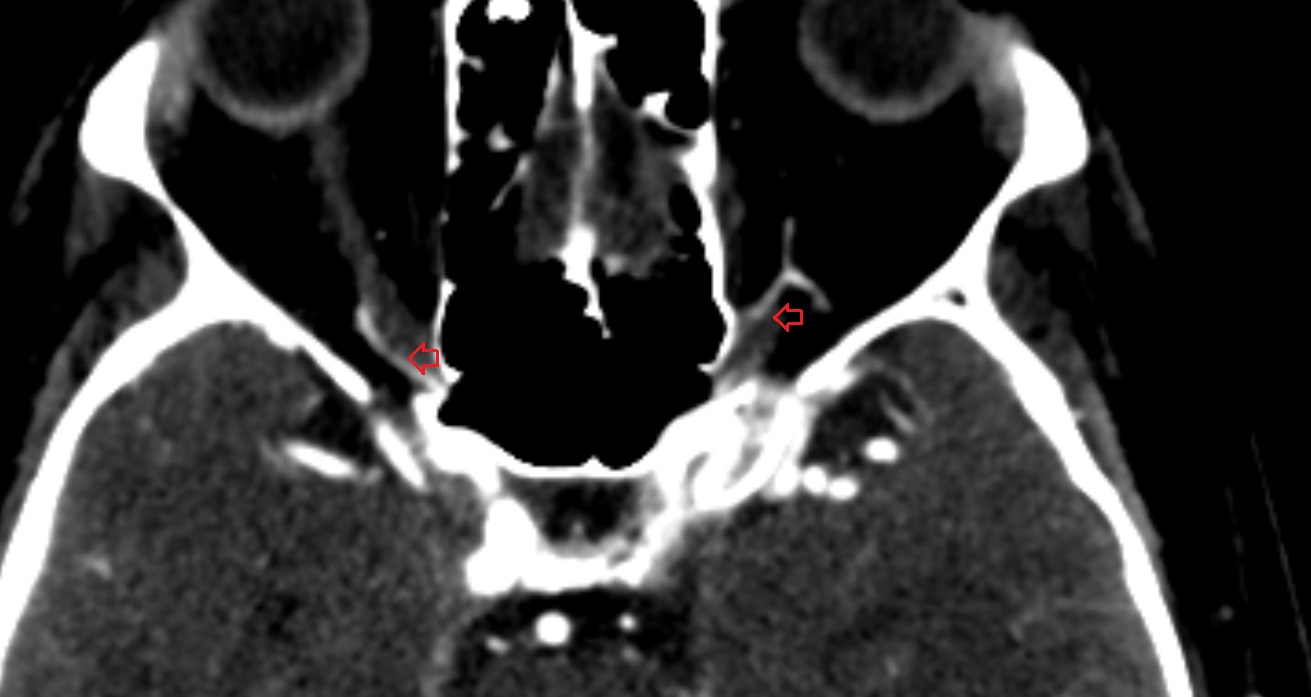

- Meckel’s cave (Trigeminal cave)